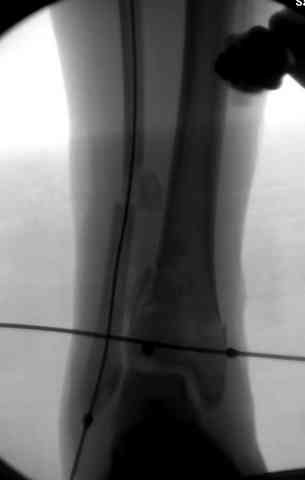

В первые часы после поступления больным экстренно накладывается простой фиксатор из двух поперечно проведенных стержней или сооружается "Delta

Frame" в зависимости от места локализации, и проводится дистракция.

Преимуществ у временного фиксатора много, во первых больной независим, если по другим показаниям нет необходимости находиться в стационаре, то больной может быть выписан домой с возможностью в амбулаторных условиях оценивать состояния мягких ткани на готовность к операции.

Наружным фиксатором обеспечивается длина конечности, предупреждается вторичное сокращение мягких ткани, что является немаловажным фактором для заживления послеоперационных ран. Без фиксатора сокращенные мягкие ткани легко травмируется во время манипуляций, трудно будет провести репозицию, ухудшается местное кровообращение и сохраняется посттравматический отек.

Дистрагированные лигаментотаксисом костные фрагменты иногда организуются в нужном направлении и во время операции облегчается репозиция отломков.

Здесь выставлена пара случаев перелома пилона, оба

случая леченные этапным наружным фиксатором.